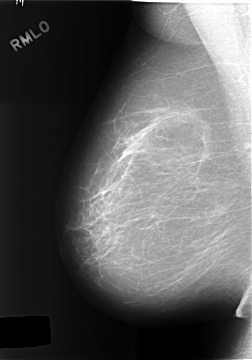

C_0469_1.RIGHT_MLO

RIGHT_MLO LINES 5760 PIXELS_PER_LINE 4024 BITS_PER_PIXEL 12 RESOLUTION 50 NON_OVERLAY